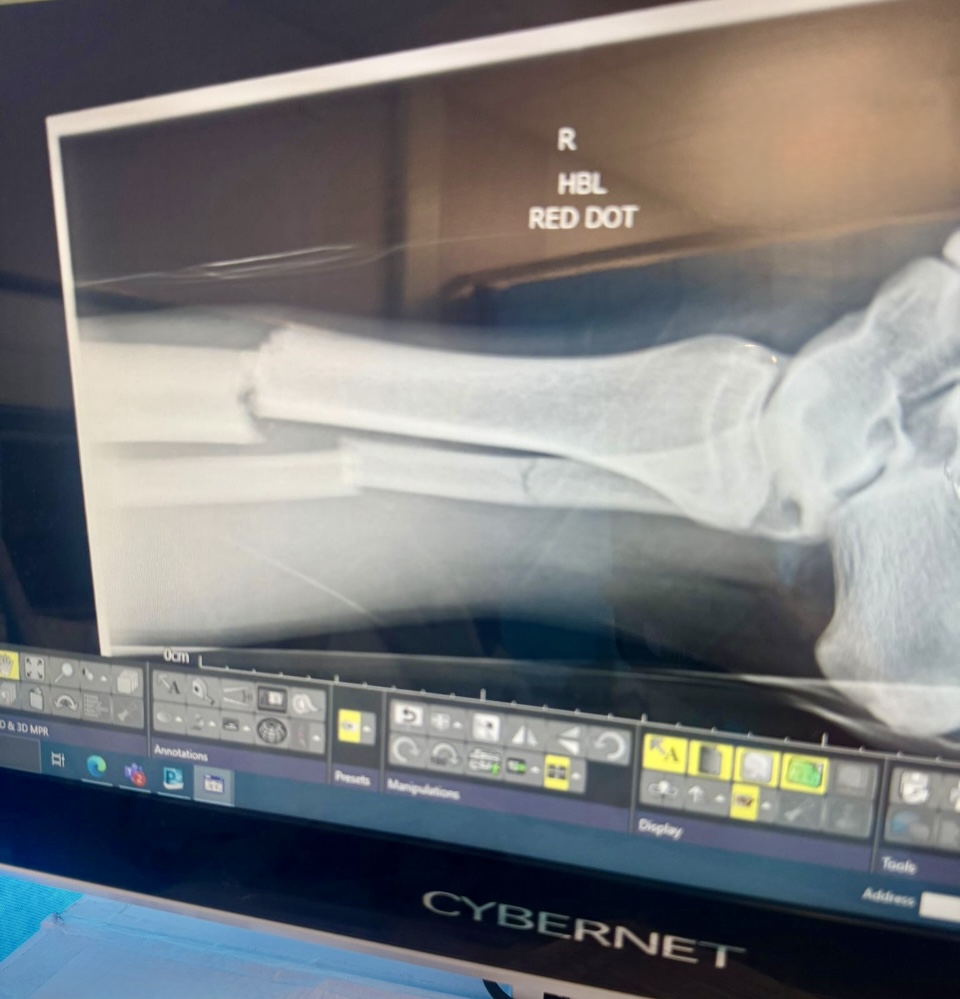

Emergency services, including both land and air ambulance teams, responded quickly, and Connor was transferred to hospital. There, he was diagnosed with five breaks to his tibia and fibula. He has since undergone surgery to repair the damage but is expected to remain incapacitated for several weeks, separated from his young family.